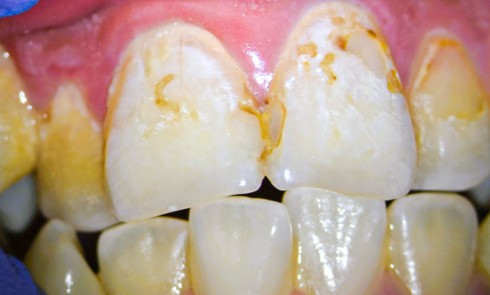

Article réservé à nos abonnés Traitement micro-invasif des lésions carieuses et hypominéralisations

Comme les thérapeutiques non invasives, les thérapeutiques micro-invasives permettent une conservation maximale des tissus dentaires et évitent le recours à...